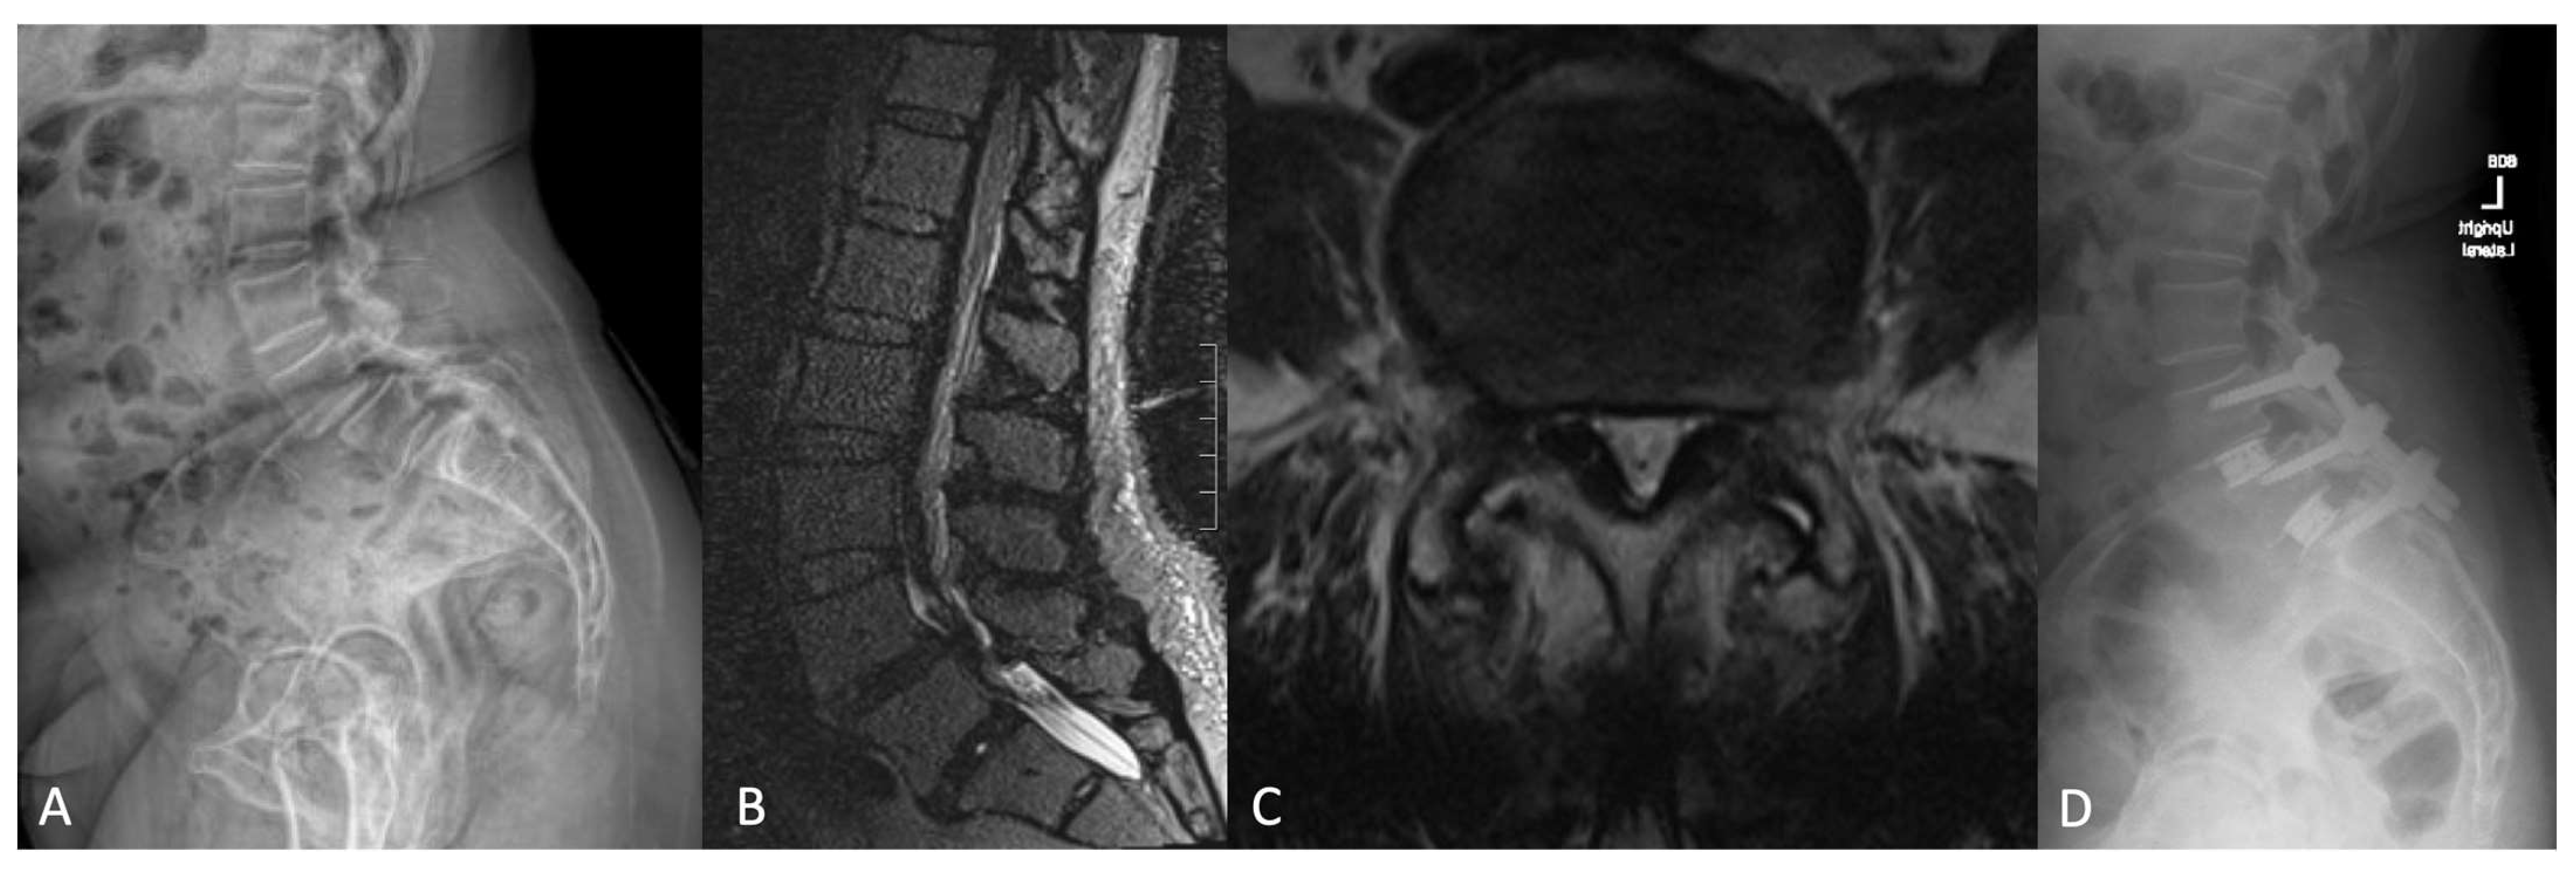

4.3. Representative Case